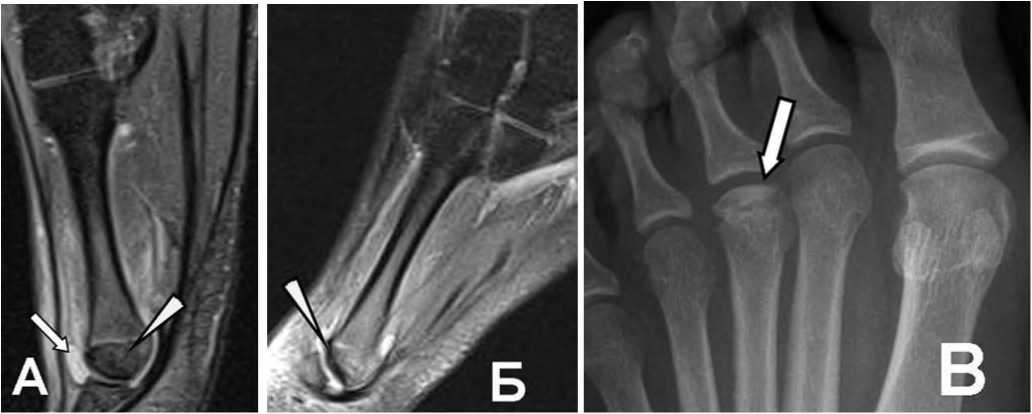

На MP-томограммах связки идентифицируются как тонкие, линейные, низкой интенсивности сигнала в Т1 FSE и PD FSE структуры, соединяющие смежные отделы костей (рис. 1А).

Рис. 1. А: Дельтовидная связка на Т1 FSE томограмме в коронарной проекции в норме: хорошо прослеживаются большеберцово-пяточный и задний большеберцовотаранный пучки (стрелки), имеющие продольную исчерченность структуры.

Обычно связки подчеркнуты окружающим жиром, имеющим высокую интенсивность MP-сигнала. При интерпозиции жира между волокнами связок выявляется своеобразная продольная исчерченность, что особенно характерно для передней межберцовой связки, большеберцово-таранного компонента дельтовидной связки, задней таранно-малоберцовой связки. Использование импульсных последовательностей с подавлением сигнала от жира позволяет точнее диагностировать разрывы и воспалительные изменения связок.

МРТ-критерии диагностики острых разрывов включают изменение интенсивности сигнала внутри и вокруг связок, прерывистость волокон, исчезновение жировых включений в структуре связки, признаки отека окружающих мягких тканей, контузию сочленяющихся костей (рис. 1Б).

Рис. 1 Б:

Разрыв дельтовидной связки на Т1 FSE томограмме в коронарной проекции, вторые сутки после травмы: полная дезорганизация волокон связки (треугольная стрелка), изменение сигнала от окружающей жировой ткани (нижняя стрелка), контузия медиальной лодыжки (белая стрелка).